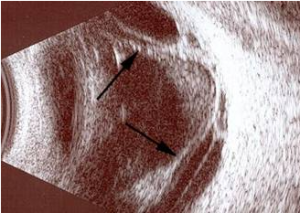

Bazı durumlarda retina, normal fundus muayenesi ile net seçilemeyebilir. Bu gibi durumlarda, göz ultrasonografisi çekilir.

Resim 9: Yandaki resimde traksiyonel retina dekolmanı olan bir hastanın göz ultrasonografisi görülmektedir. Retinanın normal yerinden öne, göz sıvısı içine doğru çekildiği izlenmektedir (siyah oklar).